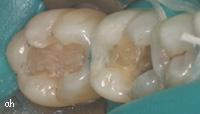

molaire avec une ancienne obturation déféctueuse

après ablation de la vieille obturation

nouveau composite en place